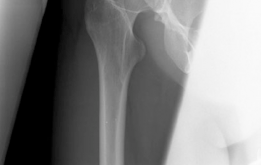

The radiographic evaluation of the dysplastic hip requires a highly standardized and rigorous protocol to accurately quantify the three-dimensional deformity. The initial assessment begins with a standing anteroposterior (AP) radiograph of the pelvis. In this patient, the AP view immediately reveals the hallmark signs of DDH: decreased anterolateral coverage of the femoral head and a broken Shenton line. The broken Shenton line—a step-off between the medial border of the femoral neck and the inferior border of the superior pubic ramus—indicates proximal and lateral migration of the femoral head due to structural instability. Furthermore, we observe an increased Tönnis angle (acetabular inclination) and a significantly reduced Lateral Center Edge Angle (LCEA) of Wiberg, confirming the diagnosis of severe lateral uncoverage.

The most critical functional radiograph in our preoperative workup is the AP Abduction view (often taken with the hip in 20-30 degrees of abduction and slight internal rotation). This view simulates the mechanical effect of a periacetabular osteotomy by effectively "rotating" the femoral head deeper into the acetabular dome. In this patient's case, the abduction view demonstrates excellent achievable congruency and congruity. The joint space becomes symmetric, and the femoral head centralizes perfectly within the socket. This is the ultimate litmus test for joint preservation: if the abduction view shows persistent incongruency or a "hinging" effect where the joint space narrows medially, a reorientation osteotomy may be contraindicated, as it would simply rotate a misshapen socket over a misshapen head, accelerating arthrosis.

With the acetabular fragment now mobile, a 5.0mm Schanz pin is placed into the supra-acetabular region to act as a joystick. The fragment is mobilized and rotated laterally and anteriorly to achieve the pre-planned coverage. We also intentionally medialize the fragment to optimize the abductor lever arm. The hip is taken through a full range of motion to ensure there is no iatrogenic anterior impingement. Fluoroscopy is utilized extensively at this stage. We obtain AP, false profile, and obturator oblique views to confirm the correction of the LCEA, ACEA, and Shenton's line, and to ensure the joint space remains perfectly congruent.